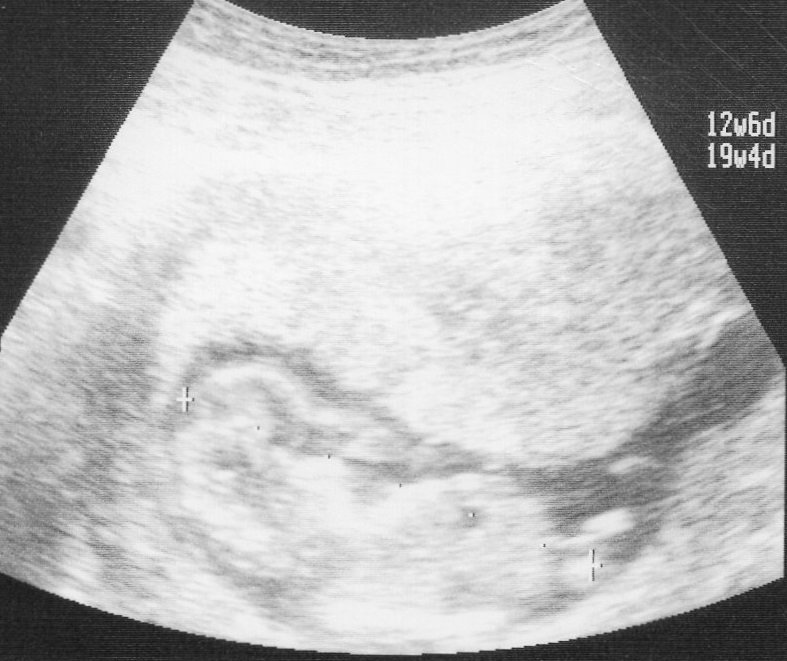

妊娠12週の妊婦のお腹の大きさは?画像あり 妊娠12週の胎児の状態は?大きさ(身長・体重)は? 妊娠12週の胎児のエコー画像画像あり 妊娠12週妊娠12週・13週・14週・15週の基礎知識ページ 妊娠12週|助産師監修お腹の赤ちゃんの成長・つわりが治まらない場合 つわりが治まってくるママも多いでしょう。胎盤が完成するころにはホ 妊娠12週 の胎児の大きさは、身長が約9cmとレモン程度の大きさ になります。この頃の胎児の体重は約gです。 この頃の胎児の体重は約gです。 妊娠12週 末には、赤ちゃんの手